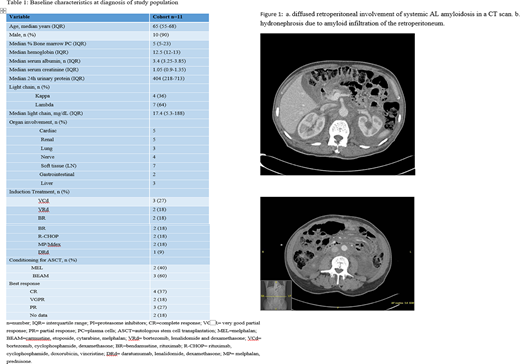

Figure 1 shows typical diffuse retroperitoneal involvement of AL amyloidosis on a CT scan.

Eight patients (72%) presented with unilateral (N=2) or bilateral (N=6) hydronephrosis and 7 had nephrostomy tubes or stents inserted. The median follow-up from stent/nephrostomy tube insertion was 33 months (IQR 8-91). Regression of the deposition was documented in one patient and one patient was able to have his nephrostomy tube removed. One patient (9%) developed end stage renal disease requiring dialysis.